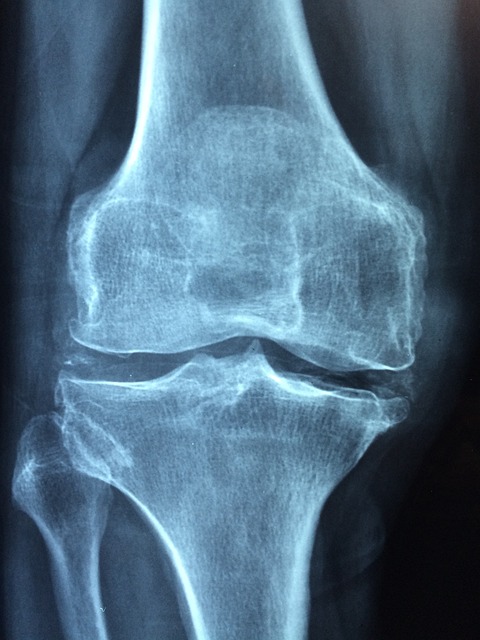

- X-레이: 슬개골과 대퇴골 사이의 정렬 상태를 평가하고, 뼈의 구조적 문제가 있는지 확인합니다. 그러나 X-레이는 연골 자체는 보여주지 않습니다.